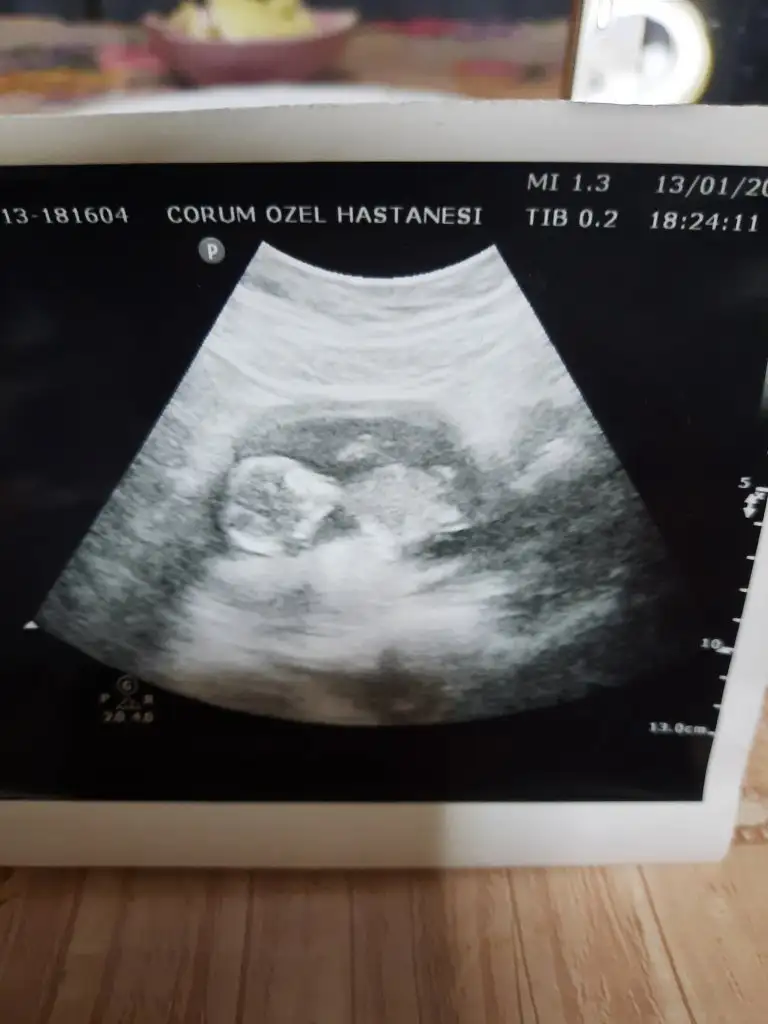

Kiz görünüyorMerhabalar 12+0 haftaligim cinsiyet tahmini yaparmisiniz isminizi temmuz annelerinden duydumIkra meyra

Erkek gibiCinsiyet ne bakabilir misiniz?Ikra meyra

Emin değilim ama sanki erkek gibi başka USG varsa paylaşınMerhaba benimkisi 12 haftalık tam. Bakar mısın lütfen. Doktor 10. Haftada erkeğe benzetti ama bugün de kız gibi dedi :)

Erkek gibi sankiBuna da bakar mısınız 12+6Ikra meyra